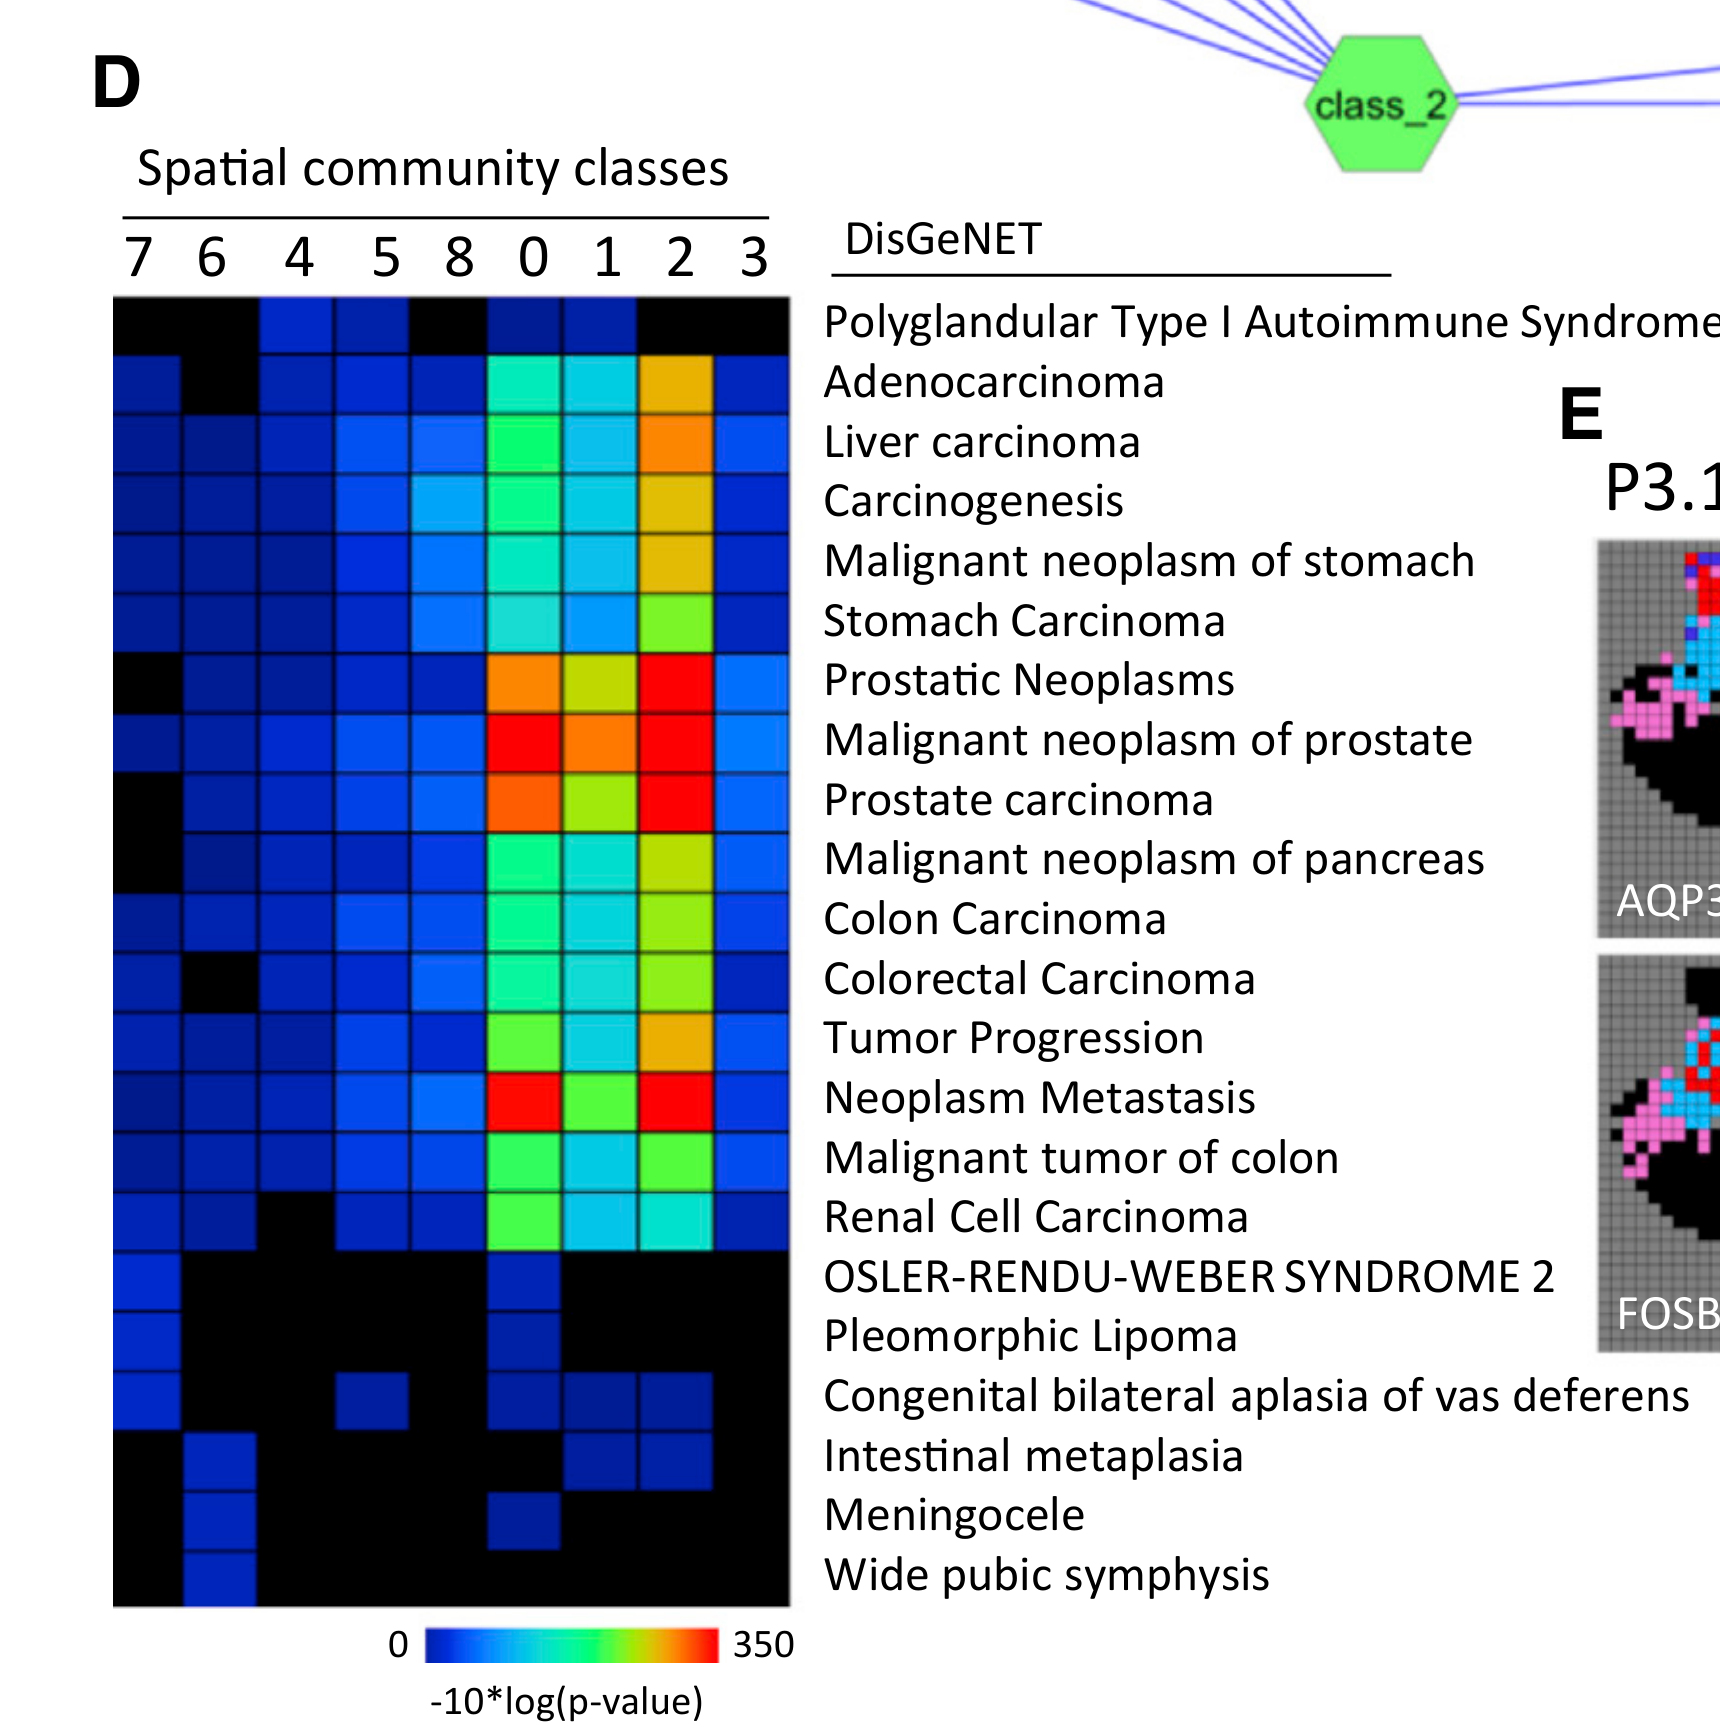

Li Y. et al. - 2024

Tissue module discovery in single-cell-resolution spatial transcriptomics data via cell-cell interaction-aware cell embedding

Condition Dimension

N/A

Data Components

Biological Annotation

Modality

Imaging-based

Resolution of observation

Cellular

Visualized Elements

Statistic

Biological

Tissue

Abstraction

Complete

Chart Type

Stacked bar chart

Communicative/Contextualization

None

Comparative Design

Juxtaposition

Layout

Linear

Scalability Strategy

Summay/Aggregate

What is the cellular composition of different spatial communities?